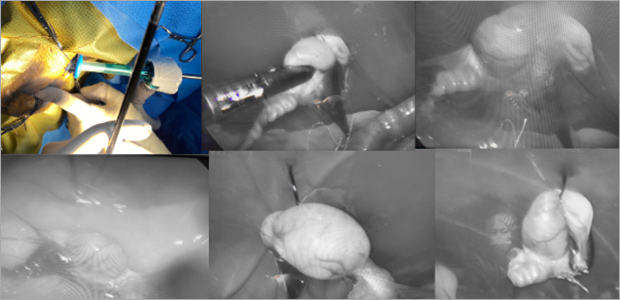

복강경 남아 잠복고환 수술

남아 잠복고환의 경우에도 전체 개복을 하지않고 최소절대 복강경 수술을 통해

복강경 카메라로 잠복고환을 찾고 기구 포트를 통해 제거합니다.

케이스1

- 수술 직후

- 제거된 잠복고환

- 수술 2주차

케이스2

- 수술 직후

- 수술 2주차